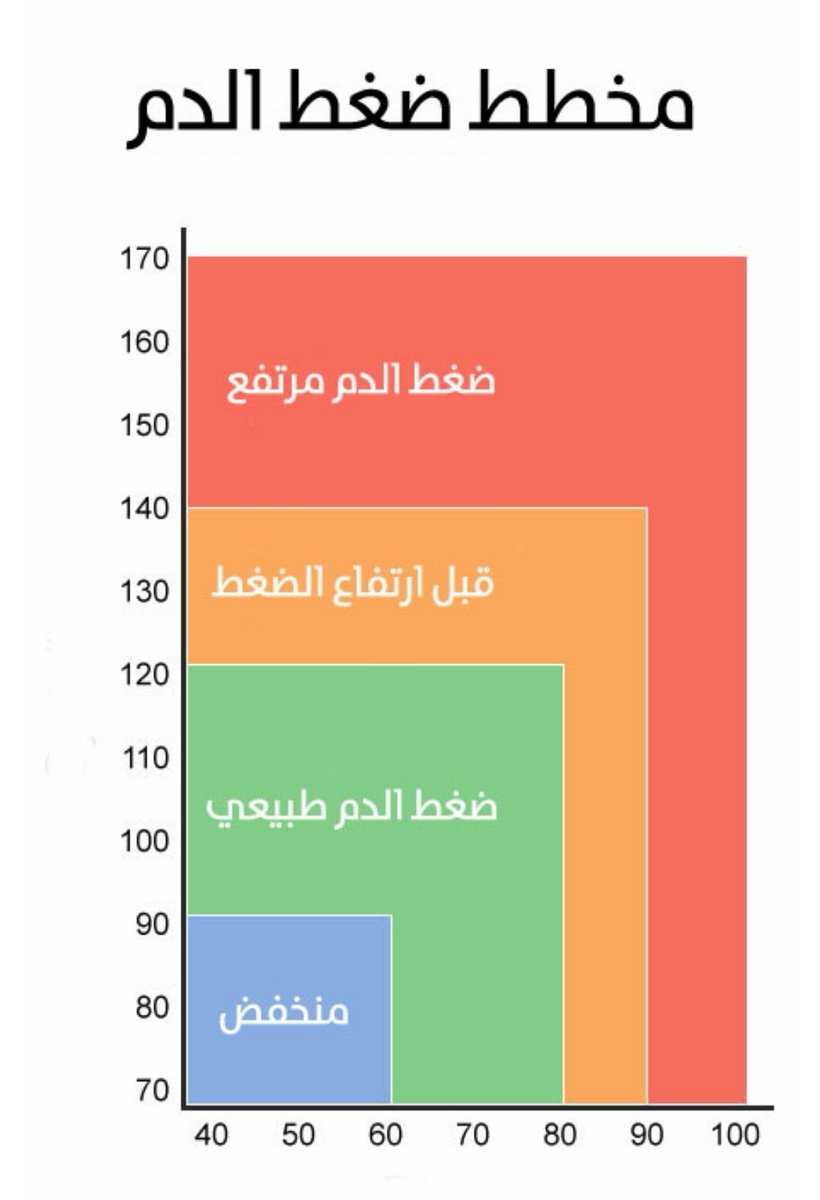

🧠ارتفاع ضغط الدم بشكل مفاجئ

🧠ارتفاع ضغط الدم بشكل مفاجئ

💥السيطرة ع #ضغط_الدم

💥السيطرة ع #ضغط_الدم

🧠ارتفاع الضغط

🧠ارتفاع الضغط